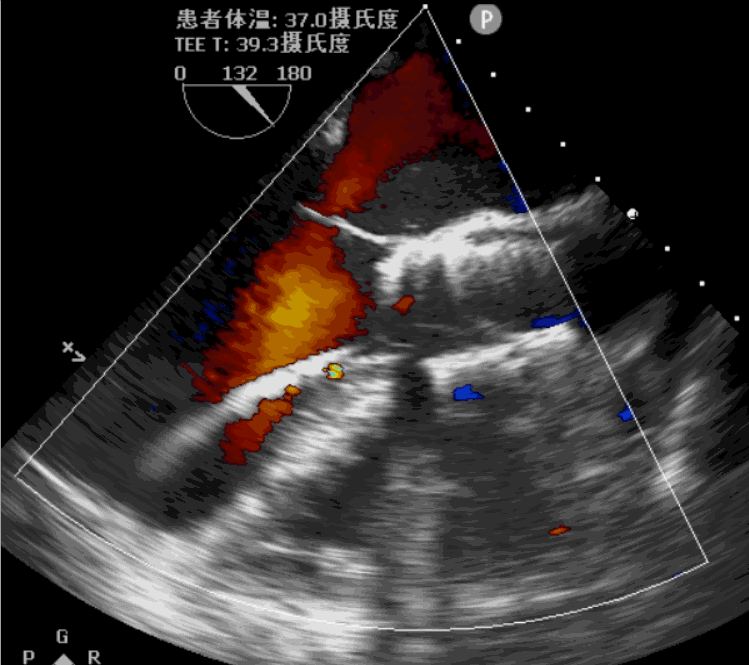

术前超声影像图

手术采用经心尖入路,对患者进行全麻后,在左侧心尖处微创手术切口仅3-4cm,在DSA及超声引导下植入JS-TAVI29#牛心包瓣膜,手术顺利完成。术前升主动脉根部测压86/47mmHg,左室压91/9mmHg,术后升主动脉根部测压87/49mmHg,左室压98/10mmHg。从导入器械到完成瓣膜置入,耗时9分钟。术后即刻主动脉瓣返流程度由术前大量返流转为消失,术后测得跨瓣峰值流速1.8m/s,平均跨瓣压差6mmHg,峰值跨瓣压差12mmHg。